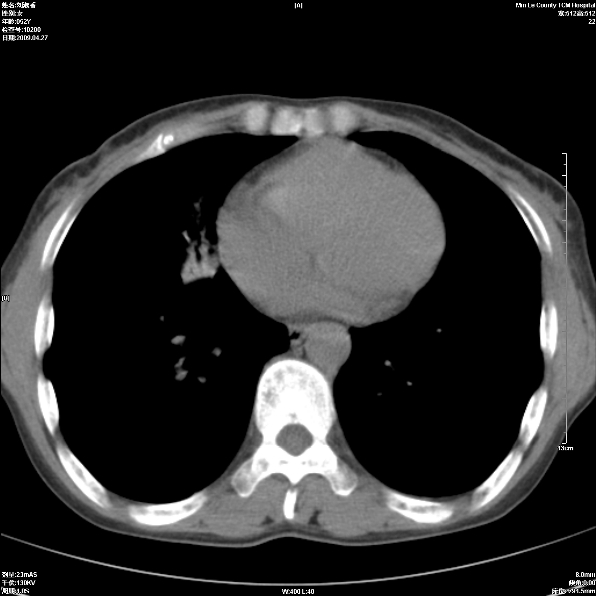

标题: CT19625:女52间断性喀血 [打印本页]

标题: CT19625:女52间断性喀血

考虑右肺中叶感染性病变并右肺中、下叶肺泡积血;建议抗炎、止血治疗后复查。

右肺中叶炎症;右肺中、下叶肺泡积血

考虑 右肺中叶感染性病变伴右肺中下叶肺泡积血。

右肺中叶慢性炎症伴局部支扩并中下叶肺泡积血。

考虑右肺中叶感染性病变并右肺中、下叶肺泡积血。建议治疗后复查。